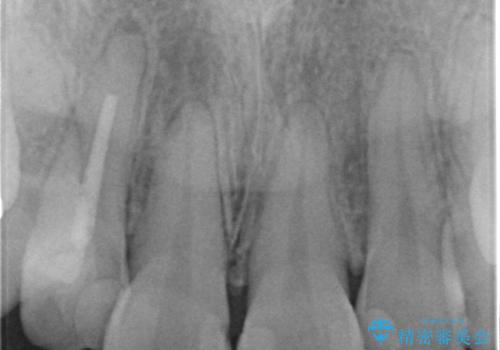

- 神経をとった前歯の変色や、前歯の充填物の変色が大きくなってきたので審美性の改善を求めて来院されました。

充填物や充填物下に再発した虫歯を丁寧に除去し、セラミッククラウンによる審美性の改善、虫歯治療を計画します。